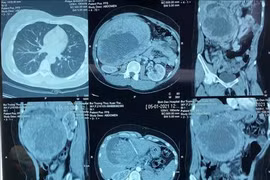

L’Hôpital général de Tuyên Quang figure parmi les rares hôpitaux provinciaux à exploiter un scanner CT à 256 barrettes. Photo : VNA

Résolution 72 : la haute technologie médicale au service des citoyens

La province de Tuyên Quang intensifie l’investissement dans les infrastructures, les équipements modernes et les ressources humaines afin de rapprocher la médecine de haute technologie des populations locales, contribuant ainsi à améliorer l’accès aux soins de santé de qualité conformément à la Résolution n°72-NQ/TW.